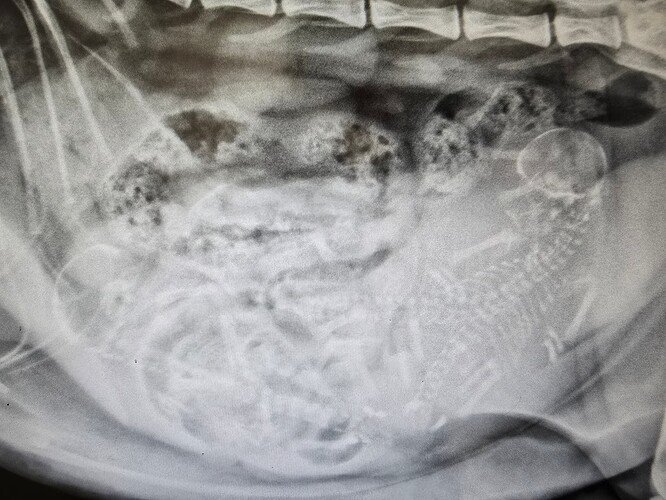

Så har vi været en tur forbi dyrlægen og fået taget røngten.

Hvor mange kan i tælle ??

Undskyld men jeg kan overhovedet ikke se nogle killinger -men jeg går ud fra, at de er der ? :wink:

Jeg er ikke ligefrem god til den slags billeder, men tror jeg ser 3-4 stykker.

Umiddelbart kun 3, men er slet ikke sikker :wink:

I fik også det svære billede :tihi:

Jeg ser tre. Men jeg er jo som bekendt dårlig til det. :sweat_smile:

Jeg kan stadig ikke se noget :ikkemig: men jeg kan da godt gætte på en 3,4, 5 stykker :grin:

Jeps der er 3 styk og som _DK_Sugieh skriver, så kigger man efter rygsøjler og ser om der er samme antal hoveder, så er man sikker på at have talt rigtig.

Jeg tror det er et fint antal til hende, hun er trods alt kun 1 år og 3 måneder, så er forholds vis ung mor